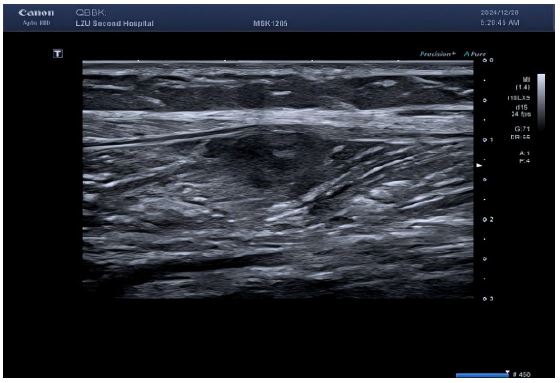

Figure 1: Multiple echogenic areas were detected in the muscle layer of the left medial calf, all with regular morphology, clear borders, and heterogeneous internal echogenicity.

Figure 2: Color Doppler flow imaging showed a small amount of short rod-shaped blood flow around the lesion.

Lower limb ultrasound: Detected a hypoechoic lesion within the intermuscular space of the right calf. Initial impression: Schwannoma suspected; CEUS recommended.

The sonographic presentation of SMM demonstrates considerable heterogeneity with limited documented evidence. Characteristic ultrasound features predominantly include hypoechoic lesions exhibiting round-to-oval or lobulated configurations accompanied by intralesional hypervascularity. Notably, many such metastases mimic abscess morphology through central hypoechogenicity with peripheral rim enhancement [6,7]. Critical discriminators from benign masses on grayscale and color Doppler imaging encompass: lobulated tumor margins, and peripheral pedicle-feeding vessels supplying architecturally disordered intratumoral vasculature [8]. Contrastingly, our two reported cases manifested atypical features diverging from conventional malignant patterns: well-demarcated boundaries with sharp tissue delineation, sparse intranodular vascular signals, and irregular avascular necrotic foci demonstrating both anechoic and non-enhancing properties—likely representing tumor pseudocapsule formation and extensive coagulative necrosis.

The reasons for the misdiagnosis of this patient as a benign tumor were as follows: (1) The initial diagnostic context involved routine ultrasound without documented extramuscular malignancy, precluding sufficient justification for metastatic suspicion; (2) Sonomorphological mimicry manifested as well-circumscribed, spindle-shaped anechoic foci with smooth margins, distinct hyperechoic capsules, and posterior acoustic enhancement within the calf musculature—features pathognomonic for schwannoma yet discordant with the infiltrative borders characteristic of aggressive malignancies; (3) Vascular analysis (Figure B) revealed sparse punctate vascular signals rather than the abundant internal/peripheral flow or large perforating vessels typical of subcutaneous cancers; (4) CEUS kinetics further reinforced misdiagnosis through arterial-phase peripheral hyper-enhancement with central non-enhancing zones, maintained circumscribed margins, and early washout in adjacent tissues—collectively aligning with classical benign enhancement profiles and creating a compelling illusion of non-malignant pathology.